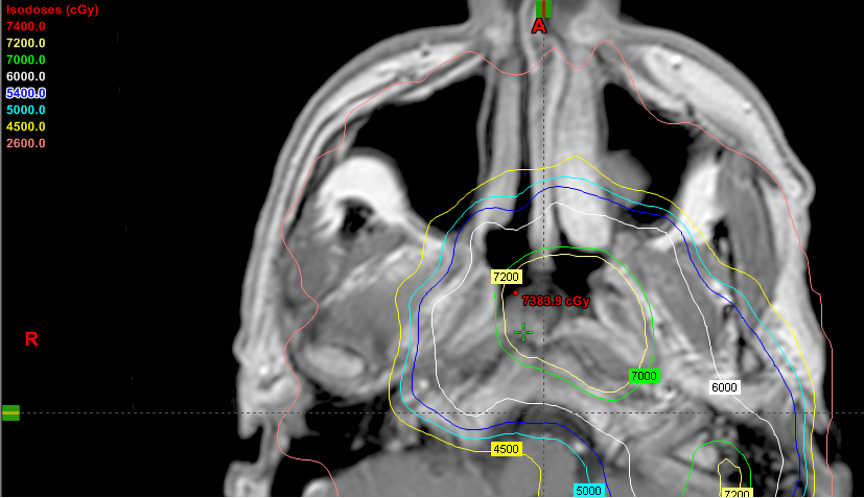

PET/CT images showing treatment planning and scale of response in metastatic rectal cancer

Stage IIIB rectal cancer initially treated with total neoadjuvant therapy followed by sphincter-sparing surgery with pathologic complete response followed by 2 additional cycles of adjuvant FOLFOX. While on surveillance, the patient presented with an elevated CEA of 18.3. PET/CT demonstrated a new 3.5 cm retrocrural node with a SUVmax of 3.5 without additional areas of FDG avid disease. Biopsy confirmed metastatic rectal adenocarcinoma. (A) Treated with involved site radiotherapy to 50 Gy in 10 fractions to the PET positive node while covering PET negative prominent paraaortic nodes to 40 Gy in 10 fractions. (B) Radiation plan demonstrating selective sparing of uninvolved bowel, liver, kidneys and spinal cord. (C) Restaging 6 month PET/CT negative. Remains on surveillance off therapy more than 3 years after treatment with a recent CEA 1.3, undetectable circulating tumor DNA and negative CT and MRI.